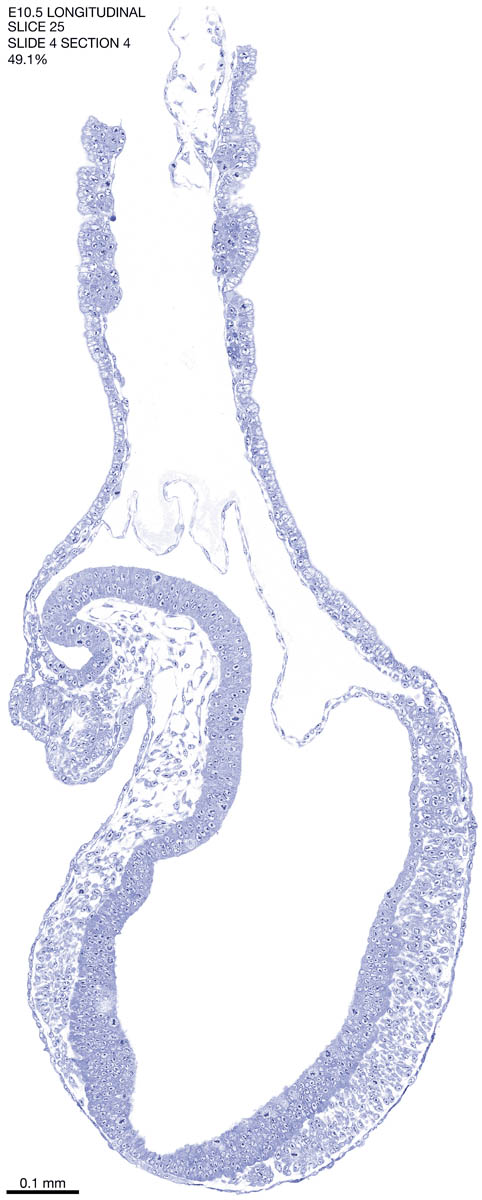

E10.5 Longitudianal Archive This page contains jpg files of ALL SLICES (each 3µm thick) that were scanned of the E10.5 longitudinally cut specimen. Download: Large | High Res Download: Large | High Res Download: Large | High Res Download: Large | High Res Download: Large | High Res Download: Large | High Res Download: Large | High Res Download: Large | High Res Download: Large | High Res Download: Large | High Res Download: Large | High Res Download: Large | High Res Download: Large | High Res Download: Large | High Res Download: Large | High Res Download: Large | High Res Download: Large | High Res Download: Large | High Res Download: Large | High Res Download: Large | High Res Download: Large | High Res Download: Large | High Res Download: Large | High Res Download: Large | High Res Download: Large | High Res Download: Large | High Res Download: Large | High Res Download: Large | High Res Download: Large | High Res Download: Large | High Res Download: Large | High Res Download: Large | High Res Download: Large | High Res Download: Large | High Res Download: Large | High Res Download: Large | High Res Download: Large | High Res Download: Large | High Res Download: Large | High Res Download: Large | High Res Download: Large | High Res Download: Large | High Res Download: Large | High Res Download: Large | High Res Download: Large | High Res Download: Large | High Res Download: Large | High Res Download: Large | High Res Download: Large | High Res Download: Large | High Res Download: Large | High Res Download: Large | High Res Download: Large | High Res Download: Large | High Res Download: Large | High Res Download: Large | High Res Download: Large | High Res Download: Large | High Res